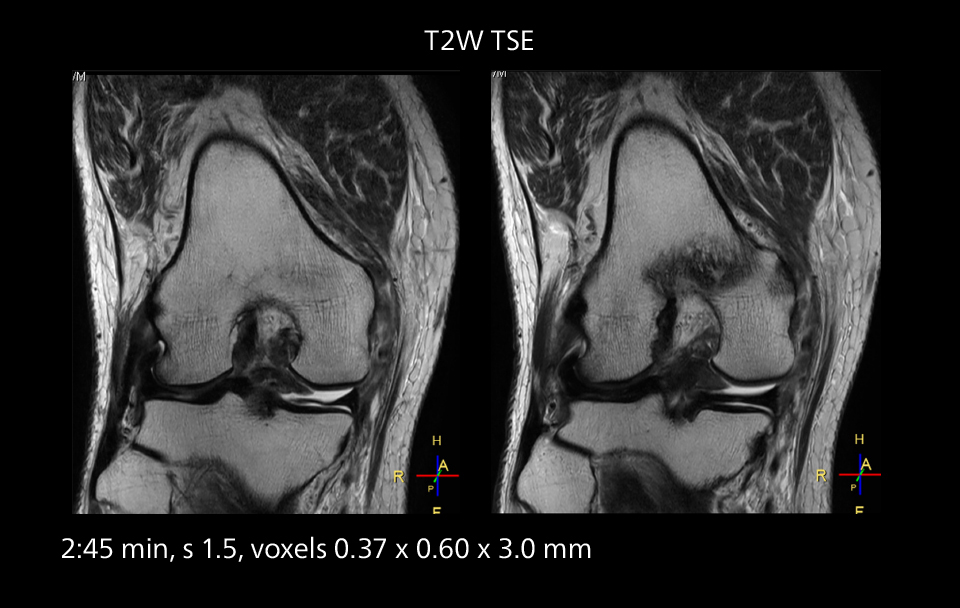

Images showing a posterior cruciate ligament (PCL) tear, a detached medial collateral ligament (MCL) on the tibial side and an intact anterior cruciate ligament (ACL). SmartPath to Elition X helped reduce scan time compared to previous imaging while maintaining resolution.

Sannodai Hospital radiologists had been very satisfied with their Ingenia 3.0T with Compressed SENSE, however after acquiring SmartPath to Elition X they have demonstrated improved image quality and even higher speeds in imaging studies throughout the body, according to Dr. Makuuchi. “Generally, we were impressed by seeing that images are very sharp and have higher SNR than we used to get with our Ingenia 3.0T system,” he notes. “We were delighted to see that high image quality can be obtained in a short time thanks to the Elition with its powerful An example of increased imaging speed is in knee studies. “There is a definite scan time reduction for T2* mFFE and proton density TSE – both of these sequences benefit from much shorter repetition times,” he reports.

Overall, imaging time per sequence has been reduced since the Elition X upgrade. This can help reduce the risk of patient movement and the need for rescans. “As our hospital has many elderly patients, we consider it important to obtain high-quality data in a short time,” Dr. Makuuchi says. “Shorter imaging times are also useful for accepting emergency patients, because faster emergency studies have a reduced impact on the daily examinations schedule. In emergency cases it is also important that high quality images are obtained in a short time.”